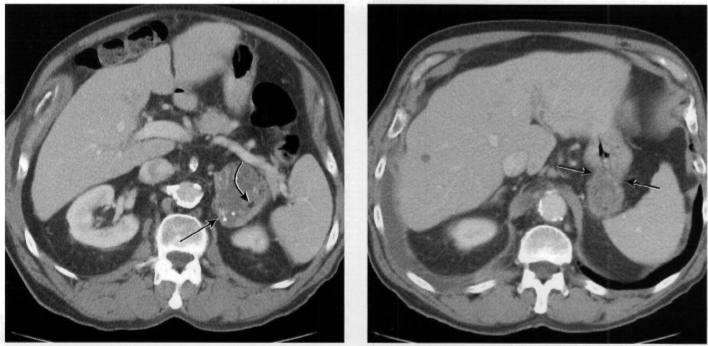

64 anos, mulher com Dor abdominal intensa

Hérnia de spiegel com sinais de estrangulamento

Colo herniário na linha semilunar, separando os músculos reto abdominal e transverso

Hérnias de spiegel tem alto risco de encarceramento (margens afiadas).

Neste caso a hérnia continha gordura omental e mostrava sinais de estrangulamento: densificação da gordura e liquido no interior do saco herniário.